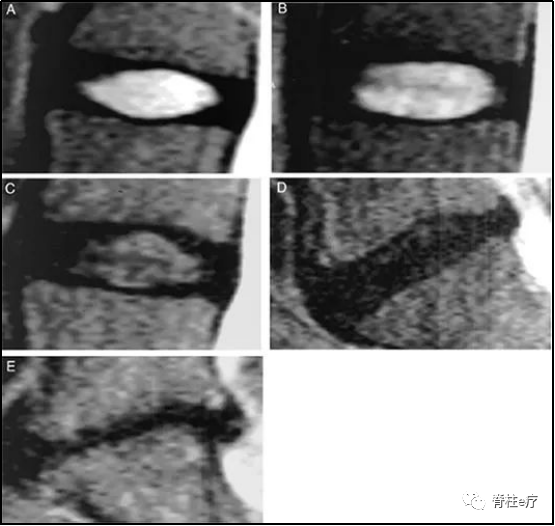

④椎间盘Pfirrmann分级

2001年,Pfirrman根据腰椎MRI对椎间盘退行性病变程度进行分级:

I级(A):椎间盘结构呈均匀亮白色信号,椎间隙高度正常;

II级(B):椎间盘结构呈不均匀高信号,髓核和纤维环间的分界清楚,椎间隙高度正常,有或无灰色水平带;

III级(C):椎间盘结构信号不均匀,呈中等灰色信号,髓核和纤维环间的分界不清楚,椎间隙高度正常或轻度降低;

IV级(D):椎间盘结构信号不均匀,呈黑灰色低信号改变,髓核和纤维环间的界线消失,椎间隙高度正常或中度降低;

V级(E):椎间盘结构信号不均匀,呈黑色低信号改变,,髓核和纤维环间的界线消失,椎间隙塌陷。

有学者通过临床研究发现中度退变(III 级、IV 级)要比轻度(II级)和重度退变(IV 级)复发率要高很多[33,34]。同时,Dota 等[35]在此研究基础上,做了更精细的研究表示:退变程度为轻度和中度时,其患者术后的复发率是重度椎间盘退变的 6.8 倍。

目前,众多学者一致认为患者腰椎间盘退变等级与椎间孔镜术后复发有显著相关性。当椎间盘退变 III 级、IV 级时,椎间盘高度正常或轻度降低,此时腰椎在生物力学上处于不稳定的状态,术后最易复发。当椎间盘继续退变、高度降低时,生物力学上腰椎节段之间重新获得了稳定,不容易复发。当然,相关生物力学的研究还需大量的临床及基础实验来证明。